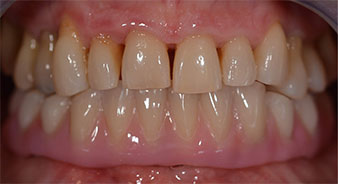

La paciente de 64 años se presentó con una dentición residual compuesta por las piezas dentales 38, 33 y 43 en el maxilar inferior y con una prótesis temporal fijada con ganchos en el maxilar inferior (figs. 1 y 2).

dentición residual

Fig. 1

Fig. 2